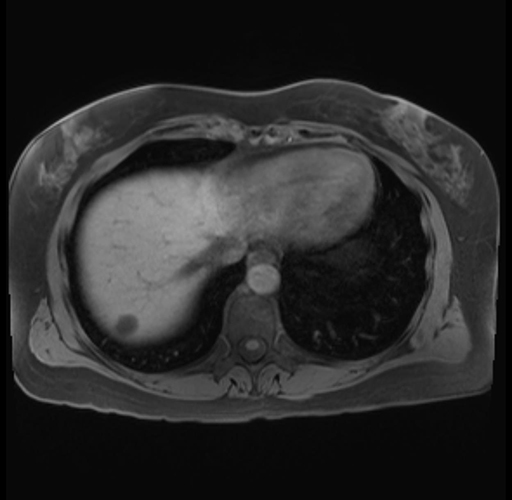

Imaging Analysis

Look through the patient's CT scan to identify any areas of concern for the necessary procedure.

Based on your CT findings, which issue(s) are present and would give reason for "planned slowing down moment(s)" in this case?